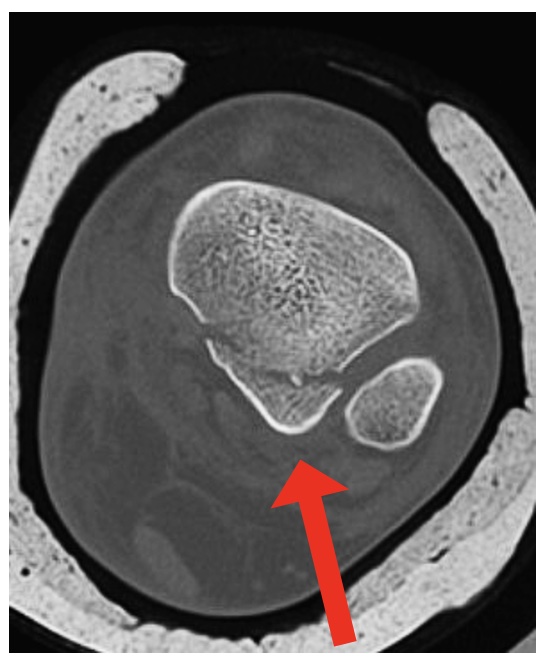

CT scan is the preferred test:

- Fracture configuration

- ‘Die-punch’ fragments

- Intra-articular fragments

Figure 1: Mason & Molloy (2017)